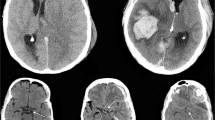

All patients in the study had non-contrast CT scan taken at the admission to hospital. Patients with only post-operative CT scans, CT angiography, or MRI scans were excluded. All available CT images were classified according to the Marshall CT classification system, the Helsinki CT score, and the updated version of NIRIS [27] by two authors (JV, RR). The CT classification systems are described in Table 1.